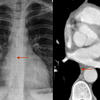

AzyEsop interf

Ex 1

Ex 1 arrows